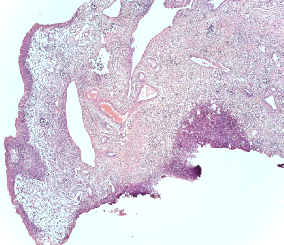

Патоморфологическое исследование пациентка О.

Морфологическая картина полипоидного цистита с наличием гиперплазированного уротелия, признаков острого и хронического воспаления, реактивной уротелиальной атипии с множественными митозами, отеком собственной пластинки слизистой с фиброзом и полнокровными сосудами и полипоидными выпячиваниями. Окраска гематоксилин-эозином, х5

Патоморфологическое исследование пациента М.

Морфологическая картина полипоидного цистита. Окраска гематоксилин-эозином, х5